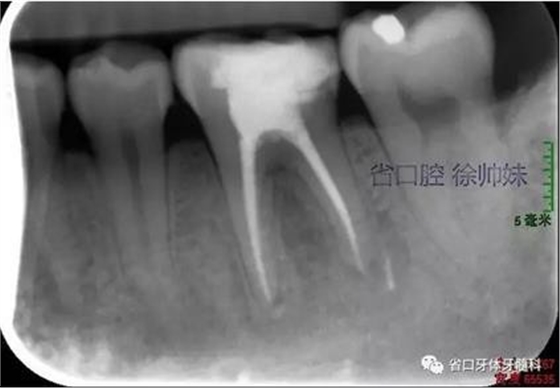

現(xiàn)病史:6個月前左下后牙區(qū)牙齦腫脹,反復溢膿,無明顯其他不適。4月前于我院牙體牙髓科(圖1)就診,診斷為“36牙周牙髓聯(lián)合病變”,建議試行36根管治療+牙周治療保留患牙,患者當時未行治療。現(xiàn)再次來我院牙體牙髓科要求進一步診治。

圖1 術前4月的根尖片